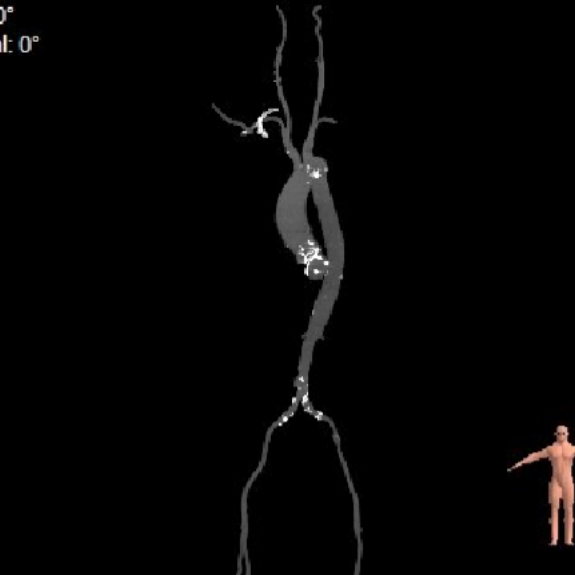

辅助检查:主动脉CTA可见腹主动脉夹层。

Part3: EVAR

EVAR

该病例同时合并腹主动脉夹层,团队同期成功实施“腹主动脉夹层腔内隔绝术”,通过微创方式置入覆膜支架,有效隔绝夹层破口、重建主动脉真腔,避免了传统开放手术的巨大创伤。对于此类主动脉瓣与二尖瓣双瓣衰败合并主动脉夹层的高危患者,二次开胸手术风险极高,而徐平、林明山教授团队凭借ScienCrown瓣膜系统的全可回收与短瓣架特性,结合经心尖途径,实现了心内双瓣膜置换与主动脉疾病介入治疗的一站式整合。为复杂心血管疾病患者提供了更具安全性、有效性和微创性的治疗新策略。